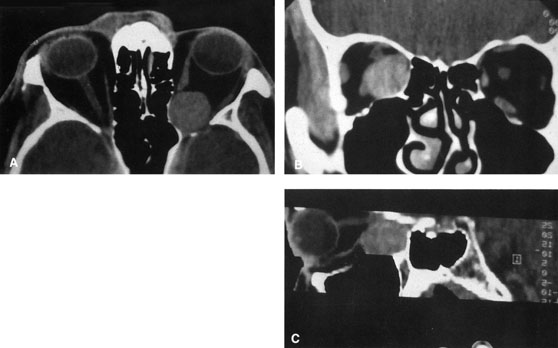

Valuable information about the nature and extent of an orbital pathologic process is provided by imaging studies such as computed tomography (CT) scan, magnetic resonance imaging (MRI), and orbital echography. Better spatial resolution, ready accessibility, and lower cost make CT the preferred choice for orbital imaging in most cases. Orbital fat provides a natural contrast between most adjacent orbital structures on CT scanning, and orbital bones are visualized well. Computed tomography is essential for evaluation of the orbital bones because they cannot be imaged with MRI. Direct coronal or sagittal images are important to identify the relationship of a lesion to the optic nerve so that the surgical approach can be planned to avoid traversing the optic nerve (Fig. 1).

Fig. 1. A. Axial CT scan demonstrating a large, well-encapsulated lesion in the orbital apex. Coronal (B) and sagittal (C) scans demonstrate that the mass lies inferior and medial to the optic nerve within the intraconal space. This information is useful in planning the surgical approach to the mass, which should avoid traversing the optic nerve.

Newer multislice helical CT scanners allow continuous acquisition of data so that a single rapid pass allows formatting in axial, coronal, and sagittal planes. Multislice CT provides shorter examination times with reduced motion artifact and radiation exposure when compared with conventional CT.